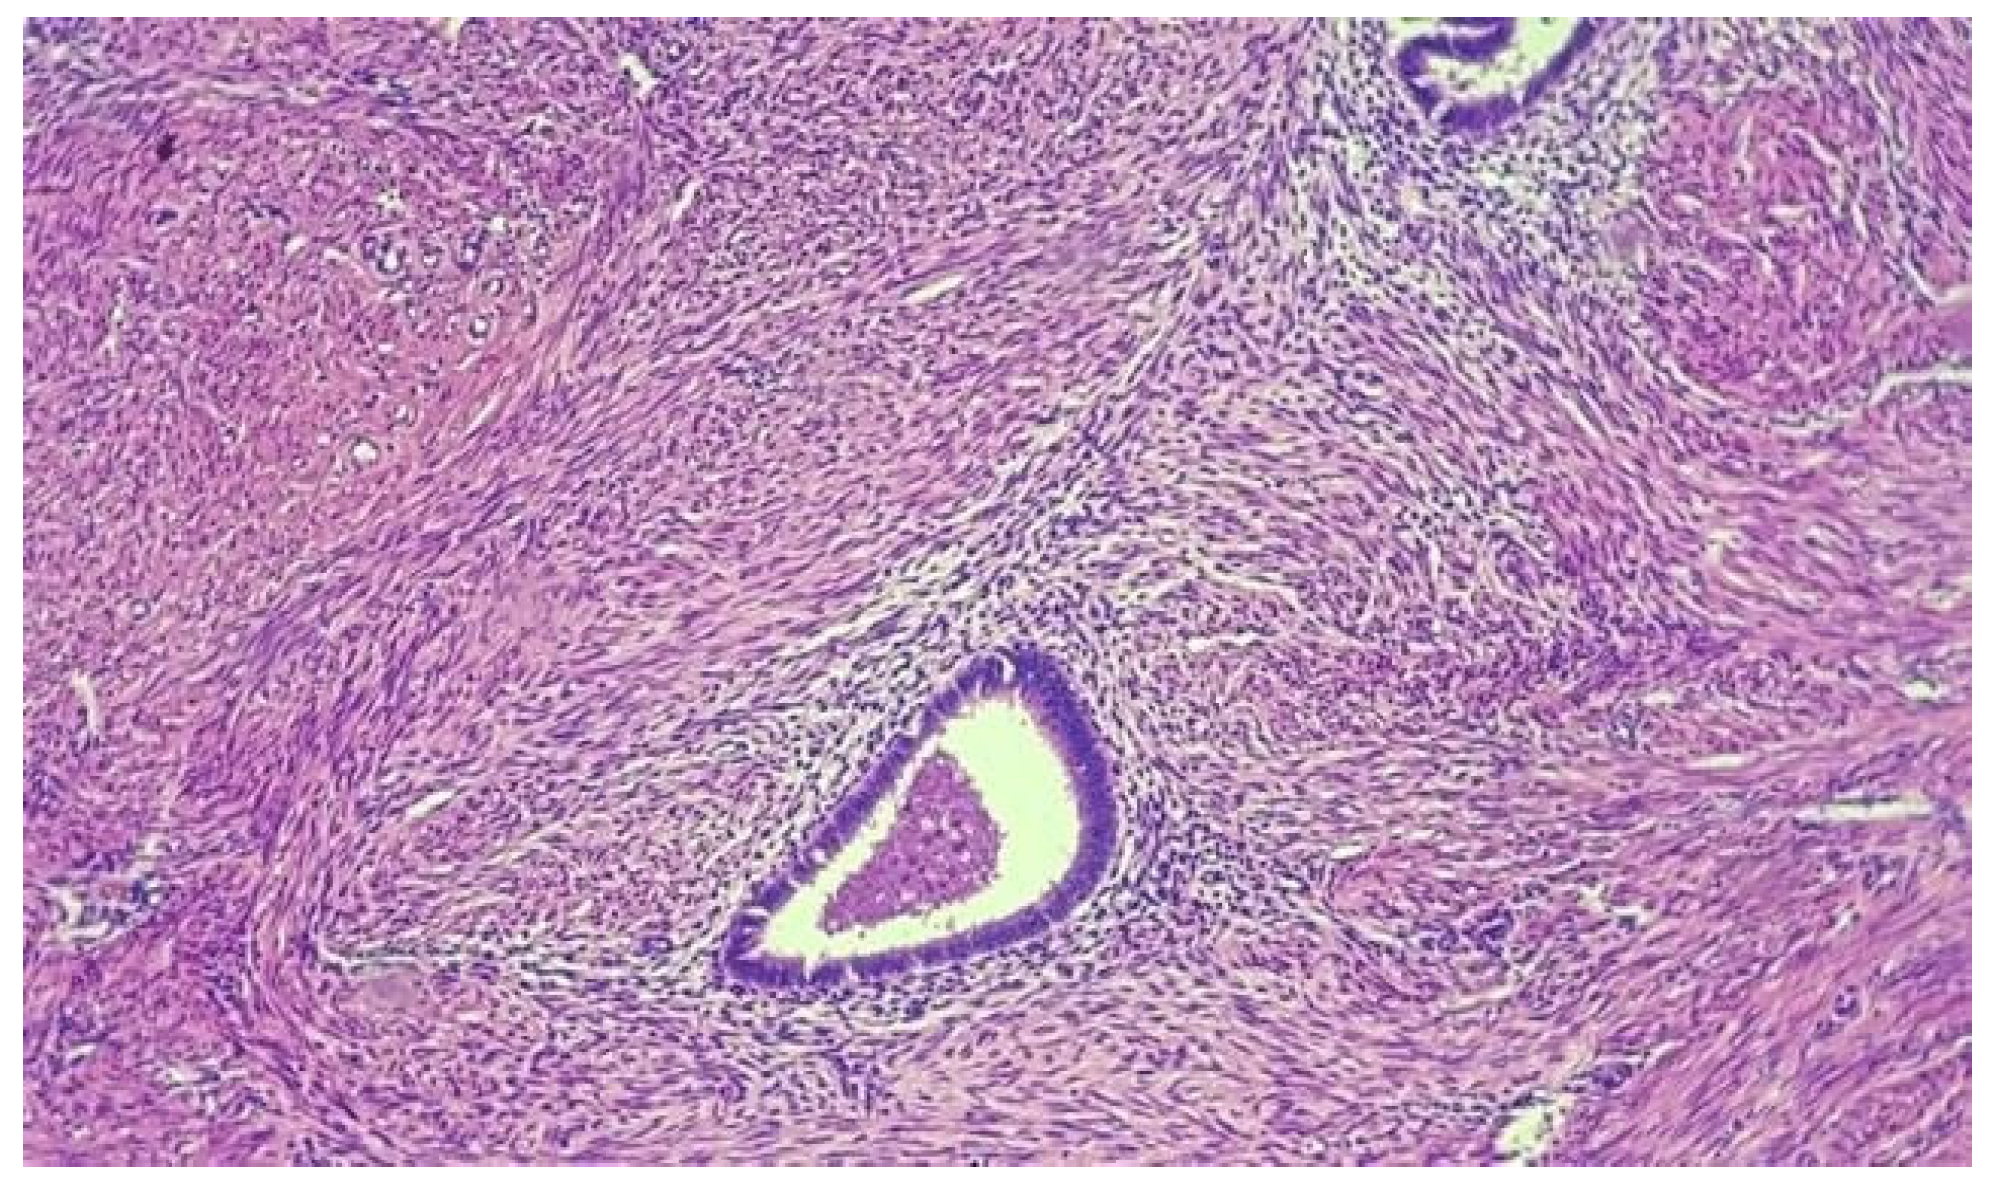

- This observation of inverse proportionality between the uterine thickness and the risk of rupture/dehiscence of the scar seems to be correlated with the histopathological features of the cesarean section scar.